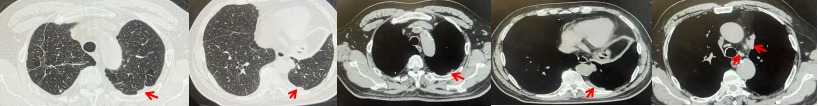

71岁男性,高血压病史20年,口服药物治疗,无糖尿病、心脏病等基础疾病,吸烟史50年,20支/天,已戒1年余,无饮酒史,无肿瘤家族史。2023.11因咳嗽、咳痰行胸CT检查:左肺下叶占位性病变,大小约12mmx8mm(如图5)。2023.11.20行“单孔胸腔镜左肺中下叶切除、肺门及纵隔淋巴结清扫、胸膜粘连松解术”;术后病理:(左肺下叶)结合免疫组化鳞状细胞癌(中、低分化),局部见脉管内癌栓,未见确切神经侵犯,(气管切缘)净。(淋巴结)未见转移癌0/19(4组0/1;5组0/1;6组0/2;7组0/1;9组0/1;10组0/2;11组0/3;12组0/2;13组0/2;14组0/4)。术后分期pT1bN0M0 IA期,术后定期复查。

2024.09.12复查胸部CT示左侧胸膜结节,大者约为27mmx13mm,考虑转移可能性大,纵隔淋巴结增大,恶性?(如图6)。患者行胸膜穿刺活检取病理,结果示(胸膜)结合免疫组化,支持鳞状细胞癌,PD-L1(克隆号28-8)TPS约20%。分期为rT0N2bM1a IVA期,DFS为10个月。2024.09.24起行替雷利珠单抗联合紫杉醇+卡铂方案治疗4周期,复查胸CT评效SD(如图7)。后患者因脑梗塞停止治疗,于综合医院就诊,后未返院复查及治疗。

图5:患者手术前(2023.11)胸部CT肺窗及纵隔窗

图6:患者胸膜及纵隔转移(2024.09)胸部CT肺窗及纵隔窗

图7:替雷利珠单抗联合白蛋白紫杉醇+卡铂治疗4周期后(2024.12)胸部CT肺窗及纵隔窗